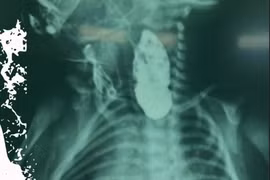

Biểu hiện của teo thực quản là sau sinh trẻ có sùi bọt cua, bú sặc, khó thở, tím tái và đặt thông dạ dày vướng.

Phẫu thuật nội soi với dụng cụ nhỏ trong điều trị gián đoạn teo thực quản là một kỹ thuật rất khó, hiếm có trung tâm Nhi khoa nào thực hiện được.